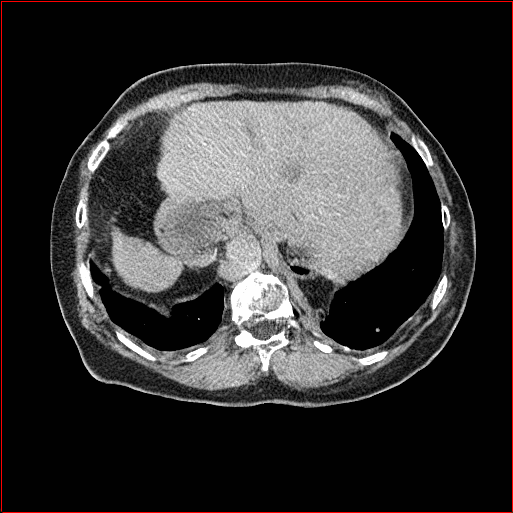

MAISI-v2 Controlnet qualitative Results:

Figure 5 shows qualitative results for MAISI-v2 Controlnet on 5 types of tumors.

Lung Tumor

0.75×0.75×0.60.75\times 0.75\times 0.6

mm

512×512×512512\times 512\times 512

Figure 5: MAISI-v2 segmentation-guided results for five types of tumors. We show results for different voxel spacing and volume size to demonstrate the flexibility of MAISI-v2. Different Hounsfield Unit window is used to better show the contrast between tumor and normal tissues.